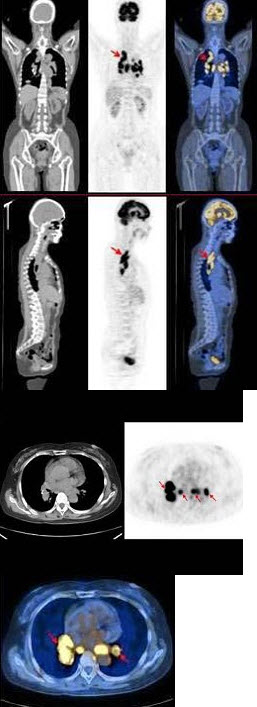

男,68岁,胸背痛3个月入院,行99Tcm-MDP全身骨显像、局部断层骨显像+X线图像融合如图,可能的诊断是()

A.胸9、10椎体良性压缩性骨折

B.大致正常的骨影像

C.胸9、10椎弓根受累,提示恶性病变

D.多发性骨髓瘤

E.胸9、10骨转移可能性大